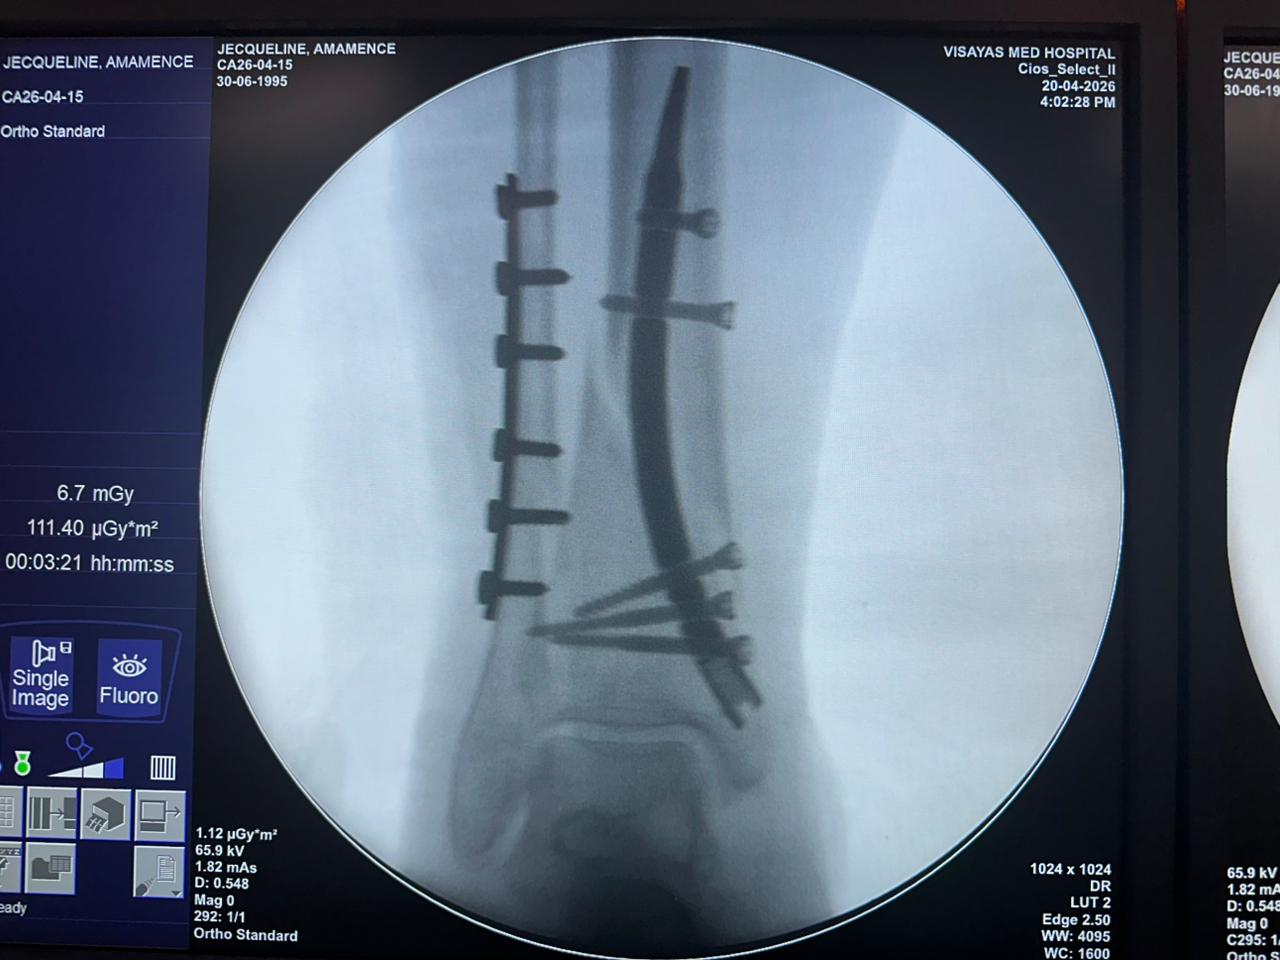

Estudio de caso de fijación de clavo tibial distal con soporte de placa para peroné

Imágenes:

Radioscopia intraoperatoria con arco en C, vistas AP y lateral

Este caso involucró la fijación de la tibia distal utilizando un clavo tibial distal intramedular. La fluoroscopia intraoperatoria confirmó la posición del clavo, los tornillos de bloqueo distales y la fijación de la placa del peroné.

caso-de-fijación-de-tibia-distal-peroné-CZMEDITECH

caso-de-clavo-tibial-distal-paciente-de-31-años-ap-view-czmeditech